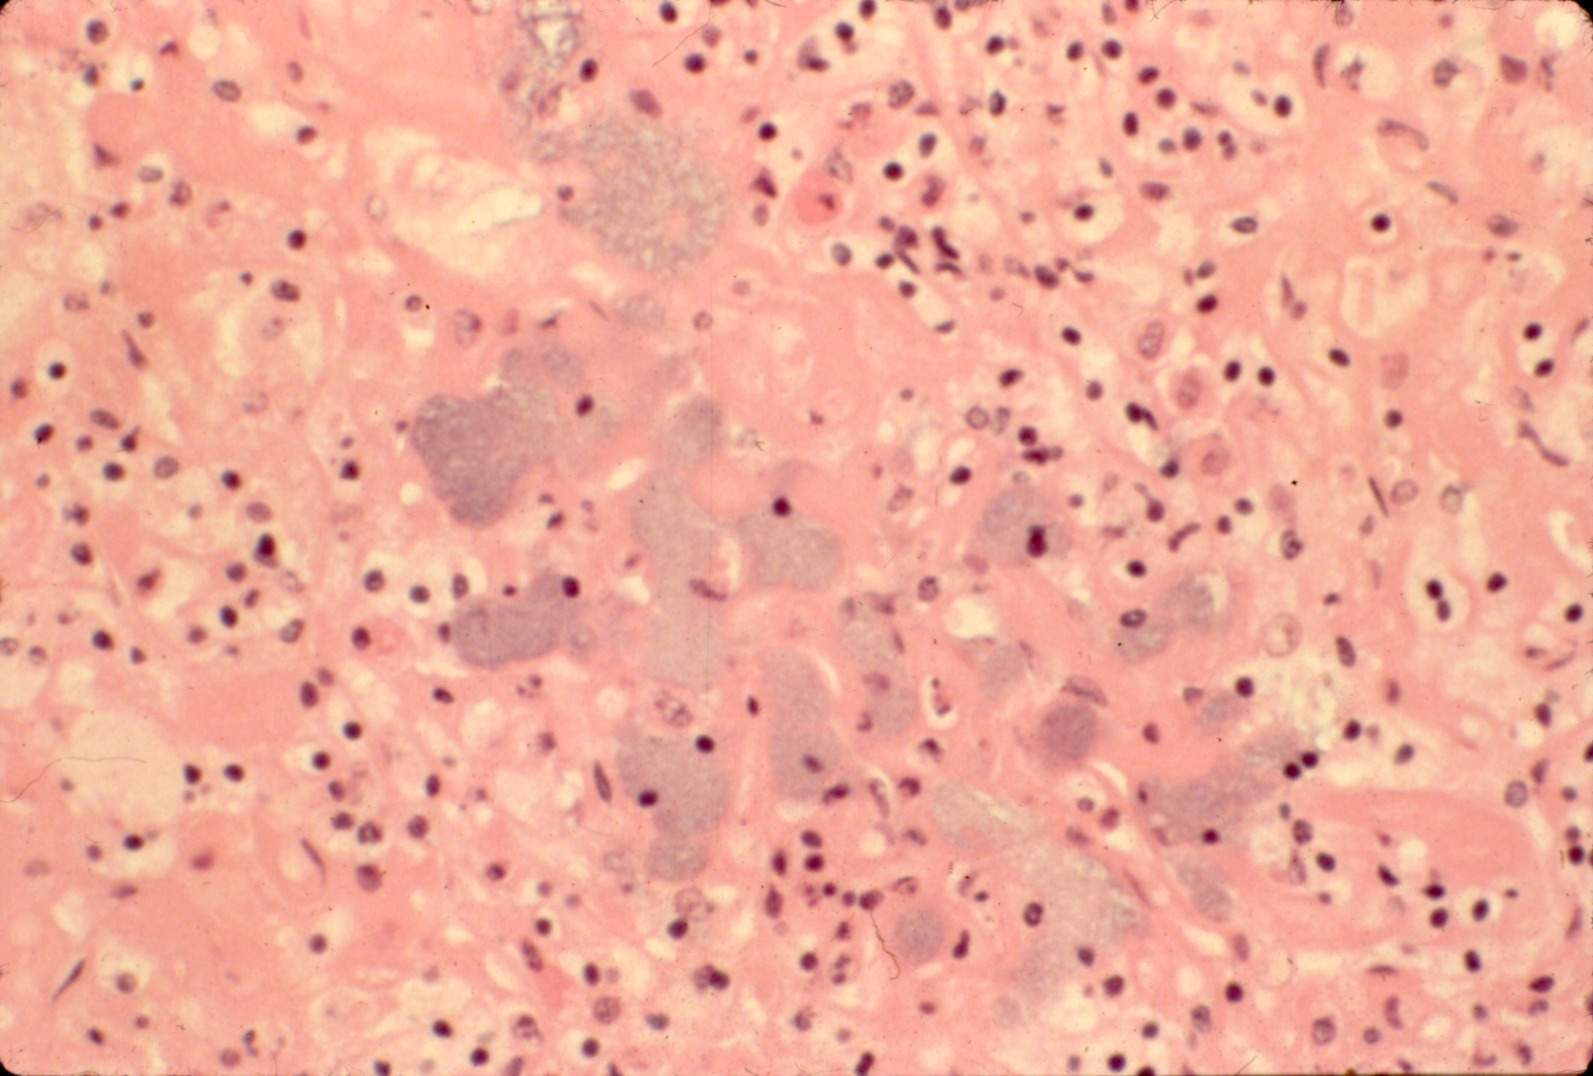

Fowl cholera (slide study set no. 19) Item Info

Fowl cholera (slide study set no. 19)

Poultry--Diseases Chicken cholera